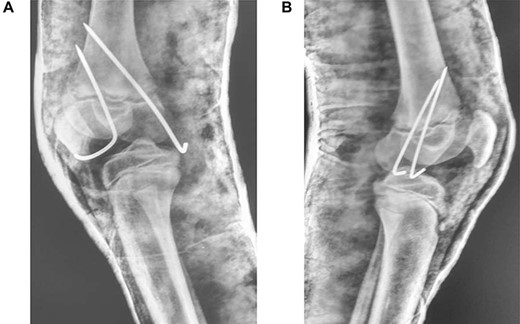

In theatre, general anaesthesia and prone positioning were performed. Closed reduction with gentle traction was achieved, followed by gradual flexion of the knee (Wilkin’s Manoeuvre). The physeal fragment was reduced with both thumbs, and reduction checked under mobile X-ray—good realignment was confirmed. Final fixation was achieved with percutaneous smooth K-wires in a cross construct (Figs 2, 3A and B). An anterior slab maintaining knee flexion was then applied. This process was repeated contralaterally. After 24 h and with adequate analgesia, bilateral foot-drop was noted. Bilateral posterior slabs were then applied.

(A) Lateral view of right knee after closed reduction, K-wire fixation and anterior slab application; (B) Lateral view of left knee after closed reduction, K-wire fixation and anterior slab application